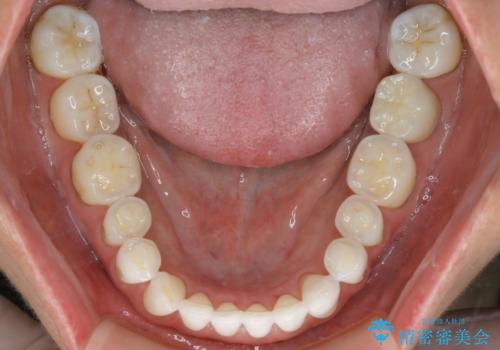

【非抜歯】マウスピースでオープンバイトを治す

- 歯ぎしりや食いしばり、噛み合わせの治療とガタつきを治したいとのことでご来院されました。

検査の結果、前歯と臼歯の高さに差があり、前歯が全く当たらない状態になっているため歯ぎしりによって奥歯が削れてしまっているという状態でした。

マウスピースの矯正装置を用い、ガタつきを治しつつ奥歯を沈めていくことで噛み合わせ全体の改善を図りました。

オープンバイト

噛み合わせや筋機能など様々な原因で前歯の噛み合わせが大きく開いている状態を開咬(オープンバイト)といいます。

原因の除去や歯牙の移動で噛み合わせの治療を行うことで改善できる場合があります。